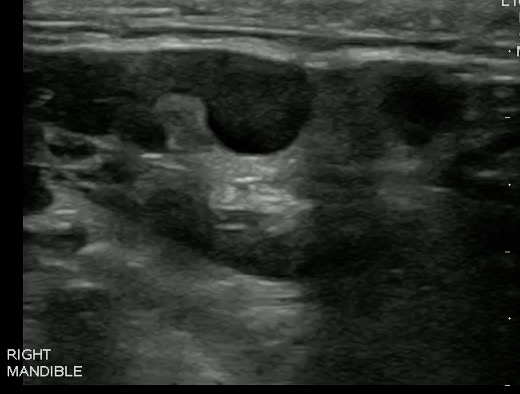

- Figure 5 and 6. Normal Mandible

- Bony structures like mandible, maxilla appear hyperechoic with a posterior hypoechoic acoustic shadow underneath.

- Fat has hyperechoic appearance on ultrasound.

- Muscles are generally visualized as hypoechoic structures but have a more heterogeneous striated appearance.

- Normal Mandible:

-

Video 4. Normal Mandible